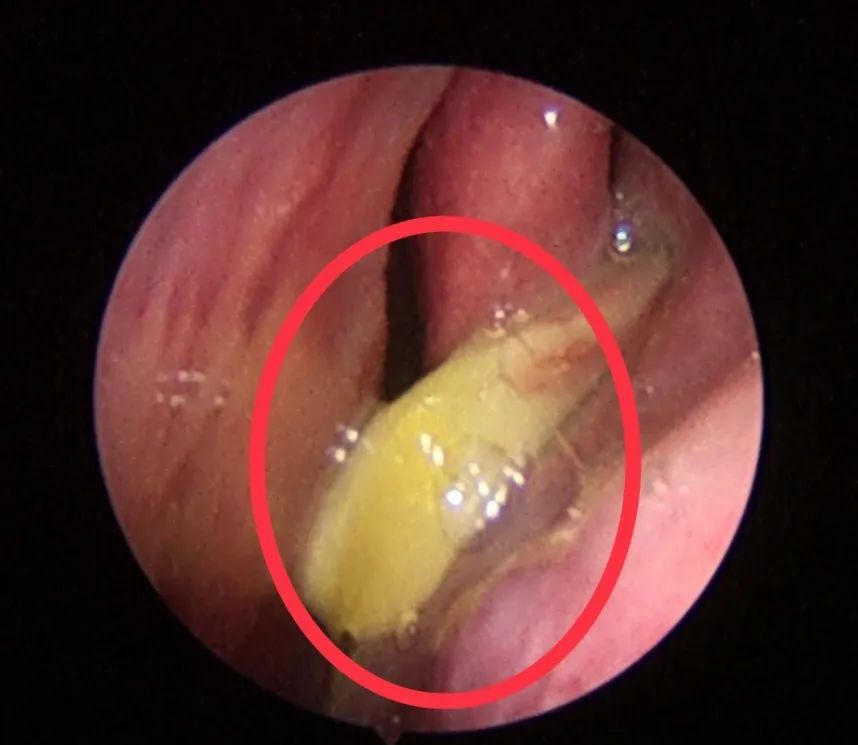

既然这多人都那么怕鼻息肉,那么真正的鼻息肉是啥样子的呢?

下面,我们来看看真正鼻息肉的面目:

其实,鼻息肉之所以让人们觉得那么恐怖,是因为它难以治根,经常复发。近年来,随着鼻内镜微创手术的开展,手术的效果还是不错的。